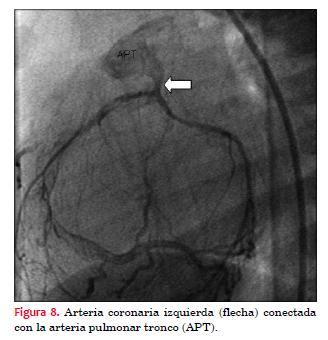

El diagnóstico se confirmó mediante aortografía y coronariografía selectiva de arteria coronaria derecha, realizadas bajo anestesia general, mediante angiógrafo Phillips Integris BH 3000, biplano, utilizando como contraste intravenoso iopromida 300 mg I/ml, utilizando 12 ml (figuras 6, 7 y 8).

Hasta hace poco tiempo la confirmación anatómica se realizaba mediante cateterismo cardíaco que permite observar: salto oximérico a nivel del tronco de la arteria pulmonar, dilatación e hipoquinesia del ventrículo izquierdo, insuficiencia mitral de grado variable, mostrar que desde la aorta solo emerge la arteria coronaria derecha, evaluar la circulación intercoronaria y a través de esta observar la arteria coronaria izquierda que se conecta con el tronco de la arteria pulmonar.